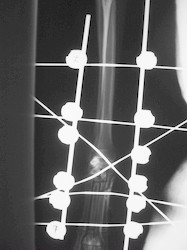

PRÁCTICAS CURSO DE FIJACIÓN EXTERNA PERFECCIONAMIENTO.

Artrodesis carpo.